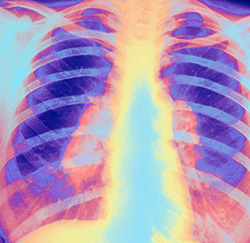

Over 40 doctors contract TB; the last doctor to be infected gets only 15 days leave

A first year female resident doctor of KEM Hospital was positively diagnosed with TB on Wednesday. However, according to the Maharashtra Association Resident Doctors (MARD), she is only being granted 15 days of leave. This is despite the fact, that TB requires 2 months of intensive treatment and care to reduce the risk of side effects and spread of the infection.

It is critical to note these important stats in light of the above case – In the last three years, 42 resident doctors have been treated for TB, 1 of them died. Presently, around 15 resident doctors are on TB treatment. Across state-run medical colleges, over 21 doctors are undergoing treatment for TB. Over the last 3 years, 11 resident doctors of KEM have contracted TB, 15 in Sion hospital, 9 in Nair and 5 in JJ hospital.